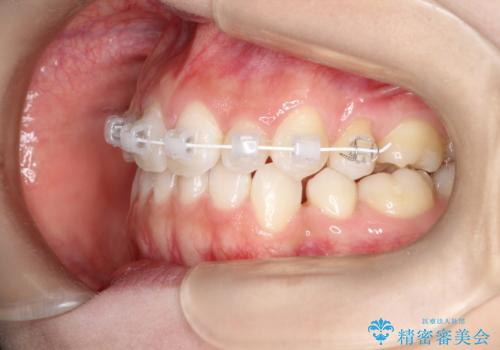

前歯の後戻りを部分矯正で整った歯並びへ

- 矯正装置

- 審美装置

- 矯正治療後の上の前歯の後戻りを気にされて来院されました。

上の前歯のみにブラケットをつけて矯正治療を行いました。